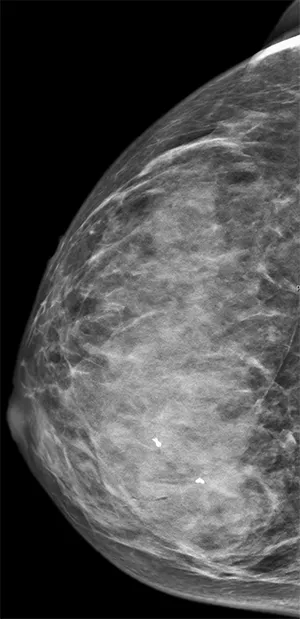

Mammographie

Die Mammographie ist ein spezielles, bildgebendes Röntgenverfahren, das der Untersuchung der Brust dient. Sie ist eine der wichtigsten Methoden zur Früherkennung von Brustkrebs und zur Abklärung von verdächtigen Veränderungen im Brustgewebe.

Bei der Mammographie wird die Brust zwischen zwei speziellen Röntgenplatten vorsichtig komprimiert. Diese Kompression ist notwendig, um die Brust gleichmäßig zu glätten und so eine möglichst scharfe und detailreiche Aufnahme zu ermöglichen. Durch die Kompression wird zudem die Strahlenbelastung reduziert und Bewegungsunschärfe vorgebeugt. Die Untersuchung selbst dauert nur wenige Minuten.

Die Mammographie kann sowohl im Rahmen der Vorsorge als auch bei Beschwerden wie Knoten, Schmerzen oder Hautveränderungen durchgeführt werden. Sie ermöglicht es, kleinste Verkalkungen, Gewebeveränderungen oder Knoten sichtbar zu machen, die oft noch nicht tastbar sind. Durch die hohe Auflösung der Bilder können auch sehr frühe Stadien von Brustkrebs erkannt werden, was die Heilungschancen deutlich verbessert.

Für Frauen ab dem 40. Lebensjahr wird die Mammographie regelmäßig empfohlen, bei erhöhtem familiärem Risiko auch schon früher. In speziellen Screening-Programmen wird die Mammographie häufig alle ein bis zwei Jahre angeboten.

Die Untersuchung ist sicher und wird von erfahrenem Personal durchgeführt. Obwohl die Kompression der Brust manchmal als unangenehm empfunden wird, ist sie nur von kurzer Dauer und notwendig, um qualitativ hochwertige Bilder zu erhalten. Die Strahlenbelastung bei der Mammographie ist gering und entspricht in etwa der natürlichen jährlichen Strahlenexposition.

Neben der klassischen Mammographie können je nach Bedarf ergänzende Verfahren wie Ultraschall oder Magnetresonanztomographie (MRT) eingesetzt werden, um die Diagnose zu sichern oder weitere Details zu klären.